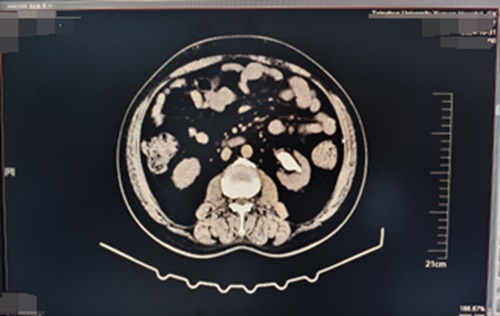

術(shù)后6周復(fù)查泌尿系CT,左輸尿管內(nèi)支架置入術(shù)后,左腎結(jié)石基本消失。

術(shù)后6周復(fù)查泌尿系CT,左輸尿管內(nèi)支架置入術(shù)后,左腎結(jié)石基本消失

微信圖片_20250112122355.jpg

在可控負(fù)壓吸引下輸尿管軟鏡鈥激光碎石取石術(shù)應(yīng)用于腎結(jié)石治療,能夠提高結(jié)石清除率,減少術(shù)中出血量、縮短手術(shù)時(shí)間、有效降低患者術(shù)后血尿、發(fā)熱、腰部不適等常見(jiàn)并發(fā)癥的發(fā)生率,為腎結(jié)石臨床治療提供了更具優(yōu)勢(shì)與效能的方案選擇。